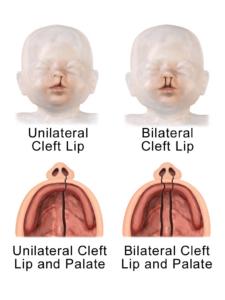

Cleft Lip and Palate

Cheatsheets

2

Mnemonics

1

Images

9

Picmonic

0